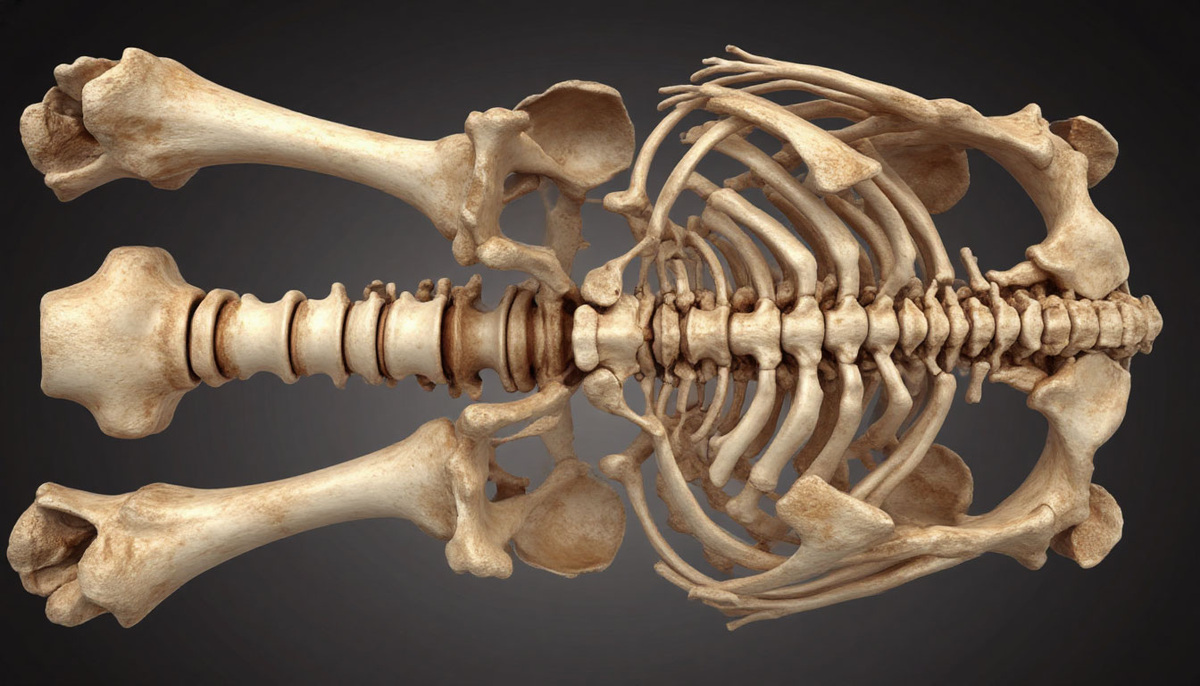

Sladekin ja kansainvälisen antropologiryhmän johtama tutkimus käsitti 1881 aikuisen ihmisen luurangon tutkimisen arkeologisista kohteista ympäri Eurooppaa. Tutkijat tutkivat olkapää-, reisiluun- ja sääriluita ottaen huomioon sekä niiden ulkomuodon että sisäisen rakenteen ja kiinnittäen erityistä huomiota luun poikkileikkauksen mekaaniseen lujuuteen. Tutkimuksen tavoitteena oli ymmärtää luiden ikääntymisprosesseja: havaita tiheyden menetystä, rakenteellisia muutoksia ja näiden muutosten vaikutusta kykyyn kantaa painoa ja kestää iskuja.

Biologisesta näkökulmasta organismi yrittää vastustaa luumassan menetystä mekanismilla, jota kutsutaan subperiostealiseksi appositioniksi ja joka lisää luun ulkohalkaisijaa tuottamalla uutta luukudosta.

Tämän prosessin tarkoituksena on kompensoida ikääntymiseen liittyvää sisäisen luuontelon laajenemista luun sisäisen resorption avulla. Tulokset osoittavat kuitenkin, että tämä mekanismi ei ole riittävä: ulkoinen kasvu ei kompensoi sisäistä menetystä, mikä johtaa luurakenteen progressiiviseen heikkenemiseen.